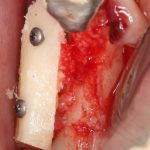

Кстати, обрати внимание на ширину альвеолярного гребня (левая картинка). Она чуть меньше 3 мм. Это объясняет, почему я засомневался в возможности установки имплантатов одновременно с остеопластикой. Понятно и без КЛКТ.

Наперво, мне нужно удалить разрушенный зуб и получить костный аутотрансплантат.

Возвращаемся к основной операционной области. Еще раз посмотрим на альвеолярный гребень, поофигеваем от его ширины и моих грандиозных планов: